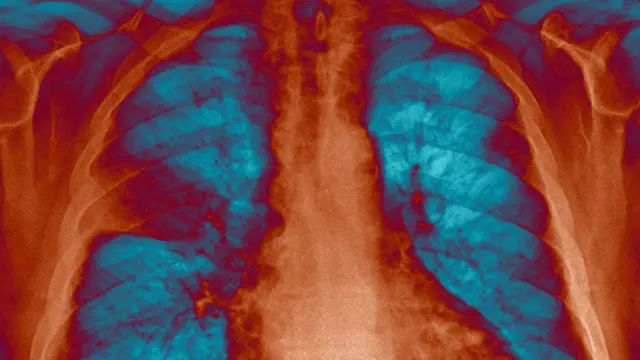

NHS Improvement的报告显示,英国的抗生素处方当中,80%是来自医院以外,而当中一半被处方作医治胸肺感染。

然而,抗生素只会对细菌感染起作用,要是感染源头是流感等病毒,处方抗生素将一无是处。